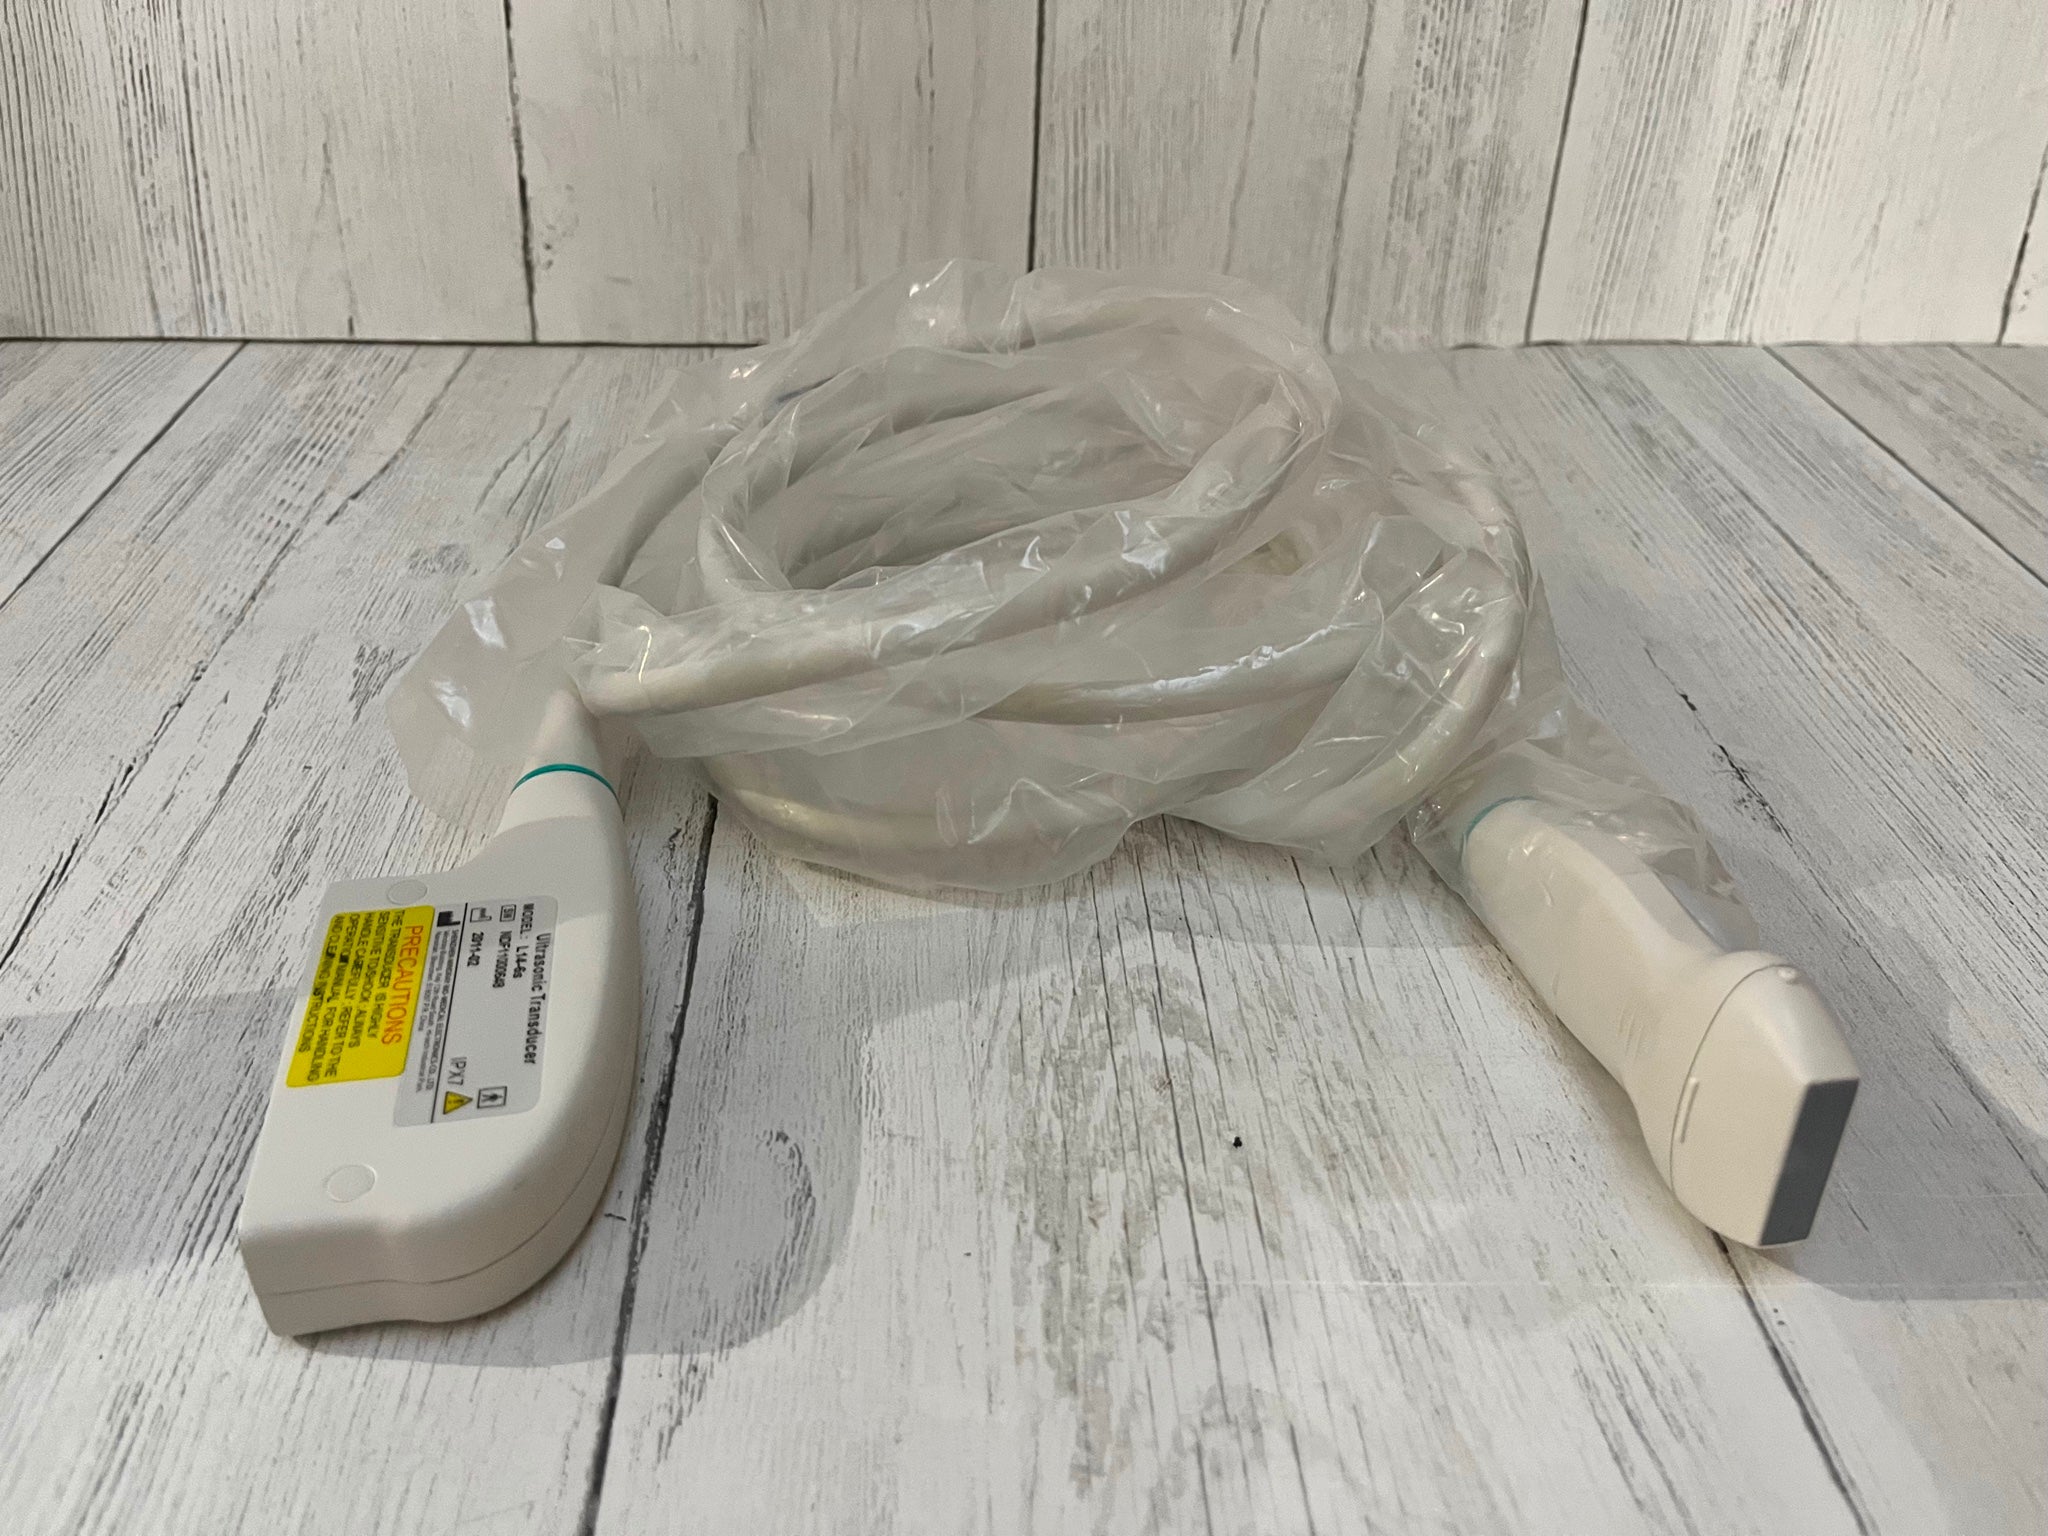

Designed with portability and functionality in mind, the New Portable Notebook Digital Laptop Machine offers superior performance without compromising on ease of use. Its compact size allows for easy transport and setup, while the digital laptop interface ensures that users can quickly access and utilize the scanner's capabilities. The inclusion of a convex probe and 3D imaging further enhances the diagnostic accuracy, providing clearer and more detailed images than ever before.

One of the key advantages of this ultrasound scanner is its versatility. It can be used in a wide range of medical scenarios, including emergency rooms, ambulances, and remote clinics. The New Portable Notebook Digital Laptop Machine is particularly valuable in situations where traditional, bulky ultrasound machines would be impractical. Because of its battery-operated design and robust construction, it can withstand the demands of frequent use in diverse environments.